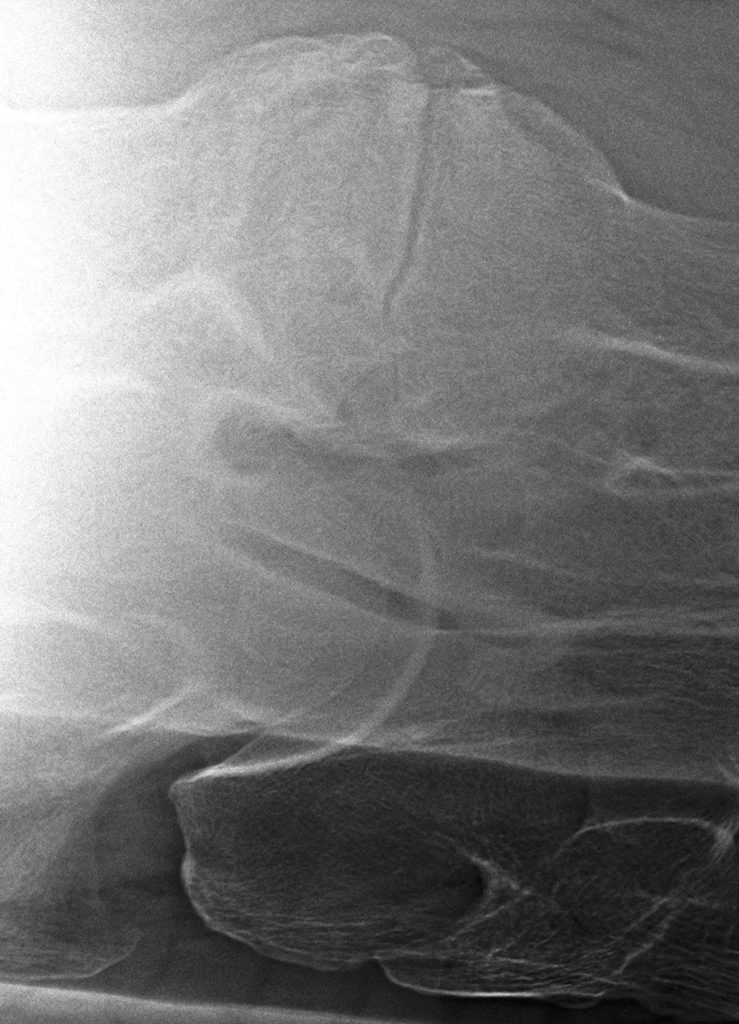

Links: Breuk in het facetgewricht

Rechts: Uitprojectie breuk facetgewricht

Breuk in het facetgewricht

Uitprojectie breuk facetgewricht